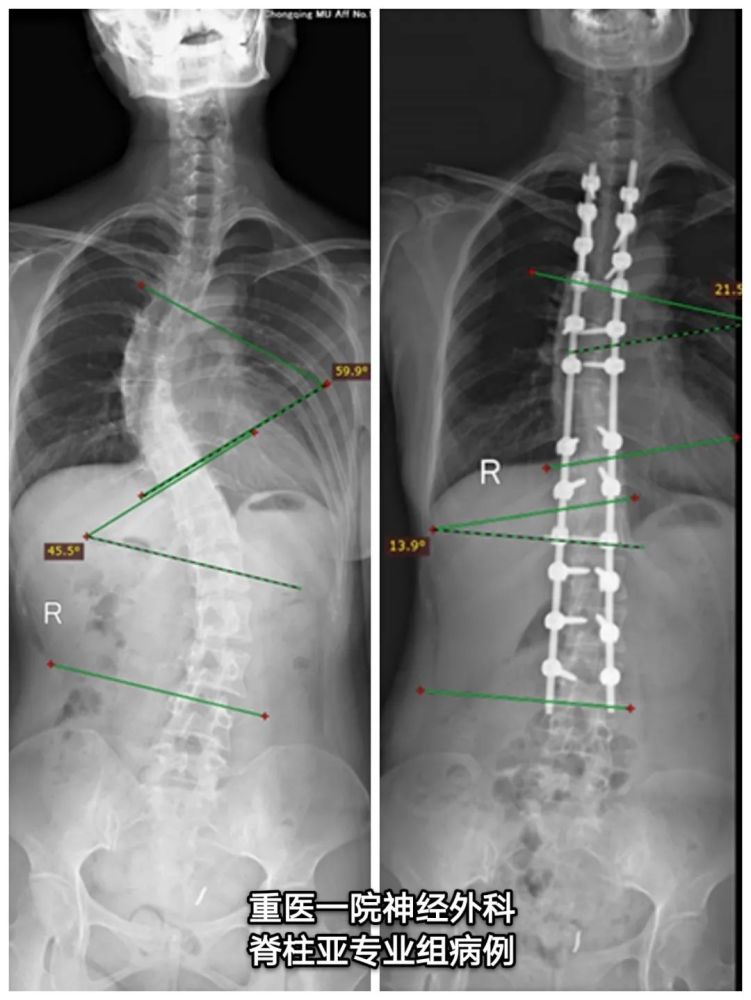

病例分享成人脊柱侧弯畸形一例